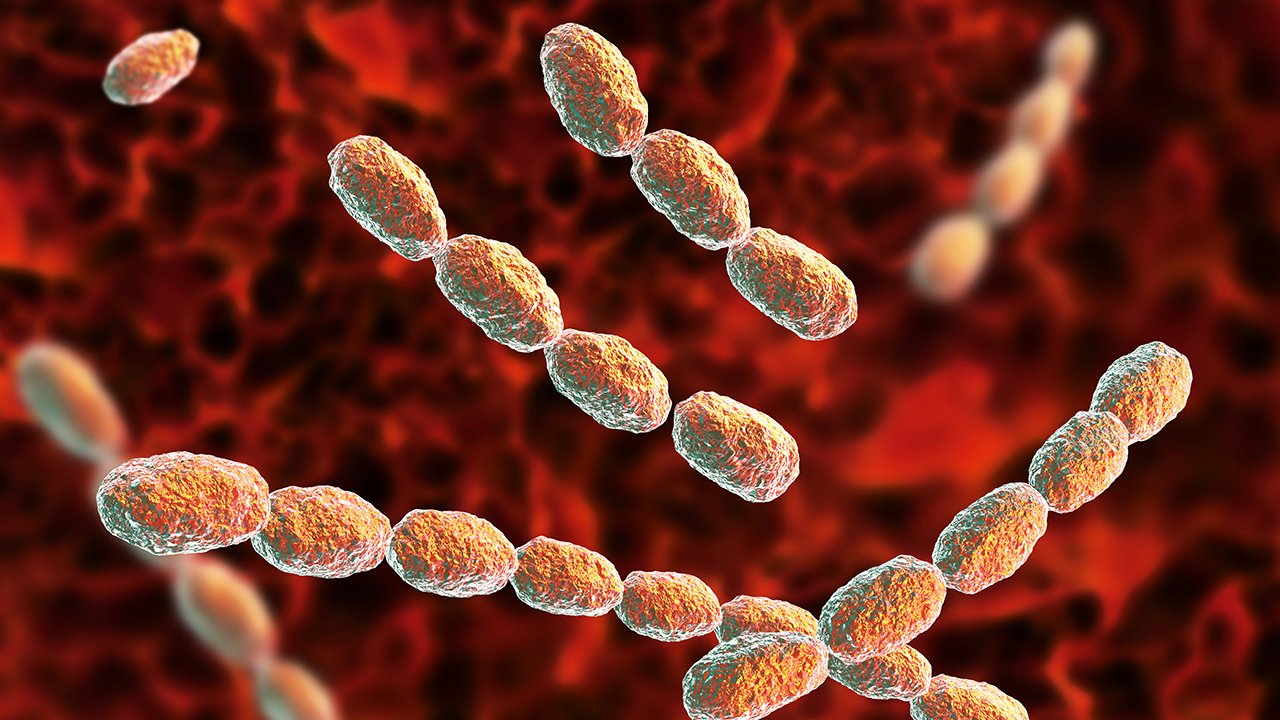

Фотографии бактерий, вызывающих бактериальные пневмонии у животных

Раздел: Другие животные